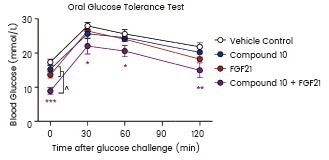

Their results showed that cells cultured with rFGF19 had enhanced cell proliferation and invasion, while FGFR4 knockdown reduced this effect. Lee et al. injected hyperglycemic mice with human recombinant FGF21 from Sino Biological to study the synergistic effect of FOXO1 inhibition and FGF21 in lowering glucose levels in diabetic mice. Their research showed that the combination treatment improved insulin sensitivity.

Blood glucose levels were measured during an OGTT performed after 11 days. STZ-induced diabetic male mice were treated by vehicle, compound 10, FGF21 (Sino Biological), or both compound 10 and FGF21. Image Credit: Yun-Kyoung Lee et al.